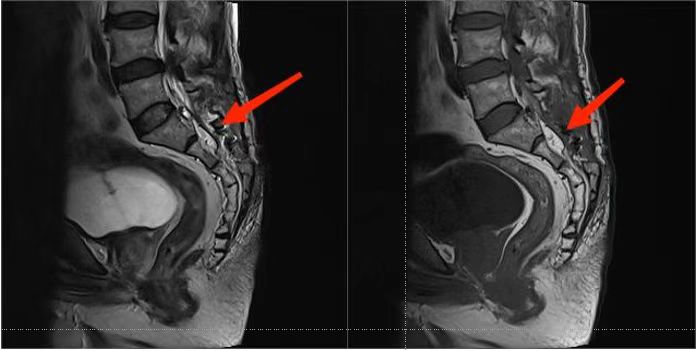

3. MRI檢查:是診斷椎管內(nèi)脊膜囊腫最可靠的檢查方法,囊腫呈長條狀囊袋形、卵圓形和不規(guī)則形等,囊液信號與腦脊液信號相似,TlWI呈低信號,T2WI呈高信號。IB型位于骶管內(nèi),與硬脊膜囊之間有脂肪相隔。Ⅱ型位于硬脊膜囊側(cè)方,囊內(nèi)有神經(jīng)根存在。

手術后骶管囊腫消失了: